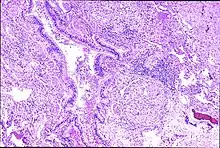

| Peribronchal non-necrotizing granuloma from berylliosis | |

With single or prolonged exposure by inhalation the lungs may become sensitized to beryllium. Berylliosis has a slow onset and progression. Some people who are sensitized to beryllium may not have symptoms.[1] Continued exposure causes the development of small inflammatory nodules, called granulomas.[3] Of note, the authors of a 2006 study suggested that beryllium inhalation was not the only form of exposure and perhaps skin exposure was also a cause, as they found that a reduction in beryllium inhalation did not result in a reduction in chronic beryllium disease or beryllium sensitization.[4]

Granulomas are seen in other chronic diseases, such as tuberculosis and sarcoidosis, and it can occasionally be hard to distinguish berylliosis from these disorders. However, granulomas of chronic beryllium disease will typically be non-caseating, i.e. not characterized by necrosis and therefore not exhibiting a cheese-like appearance grossly.[5]